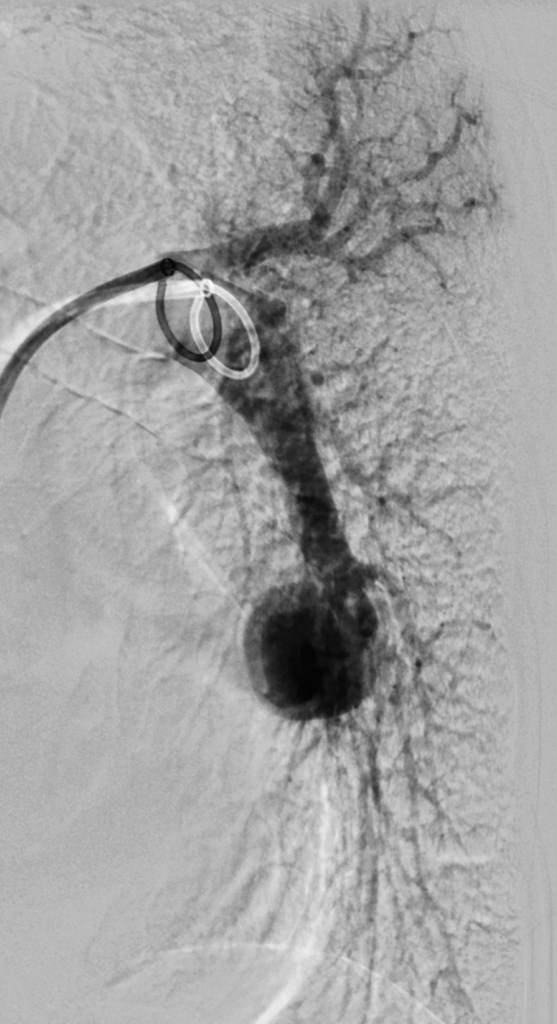

Bild 1:

Angiogramm der Lungengefäße mit Nachweis einer großen (hier kugelförmigen) arterio-venösen Malformation der Lunge